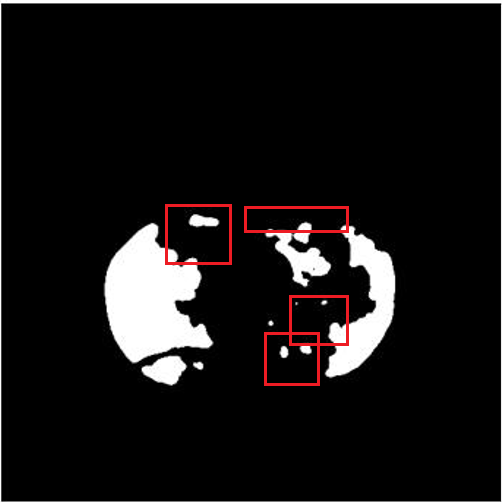

(a) Lung CT scan

(b) Ground Truth

(c) Prediction by FuDSA-Net

(d) Prediction by -Net++

The resultant segmentation map of FuDSA-Net is observed to be relatively more accurate and closer to the corresponding ground truth, as illustrated in Fig. 3.